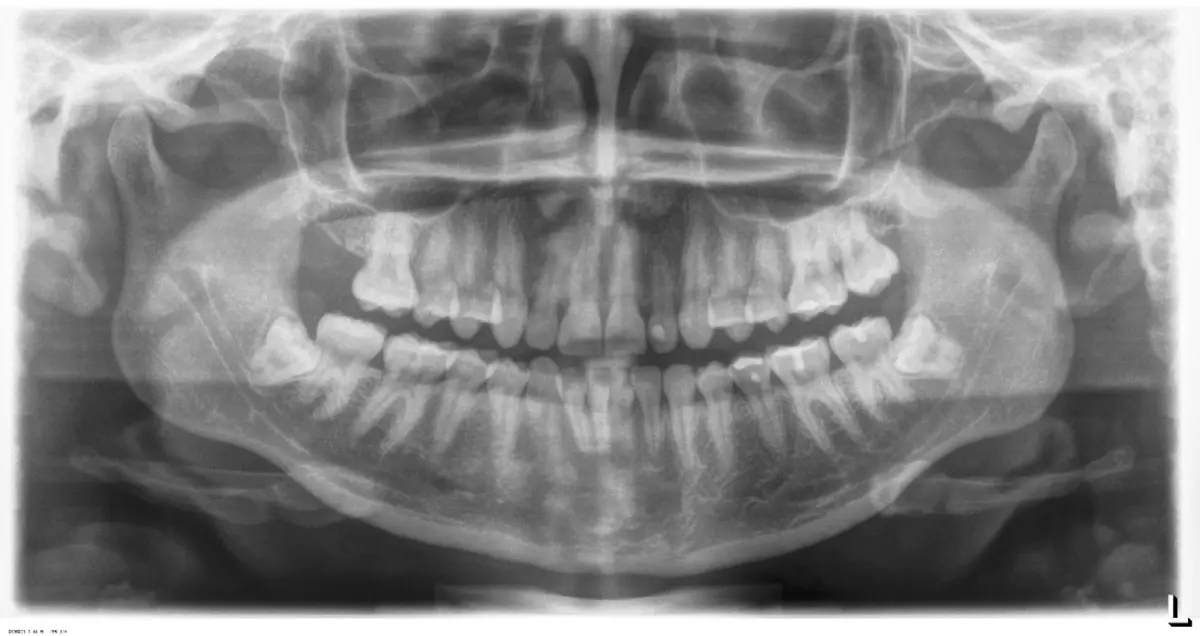

Paciente de sexo femenino con 34 años, acude a consulta por molestia en la zona 38. Clínicamente se observa zona edematizada, sintomática a la palpación. Presenta apertura ligeramente limitada, crepitación unilateral en ATM (articulación temporomandibular) derecha, asintomática a la apertura o cierre articular. En el examen imagenológico se confirma impactación dental con posible compromiso distal de la pieza 37. Pieza 38 en relación IIIC (Pell-Gregory,1993) y posición mesioangulada (Winter, 1926) con aparente formación incompleta de raíces.

Figura 14. Vista radiográfica de la situación de la paciente.